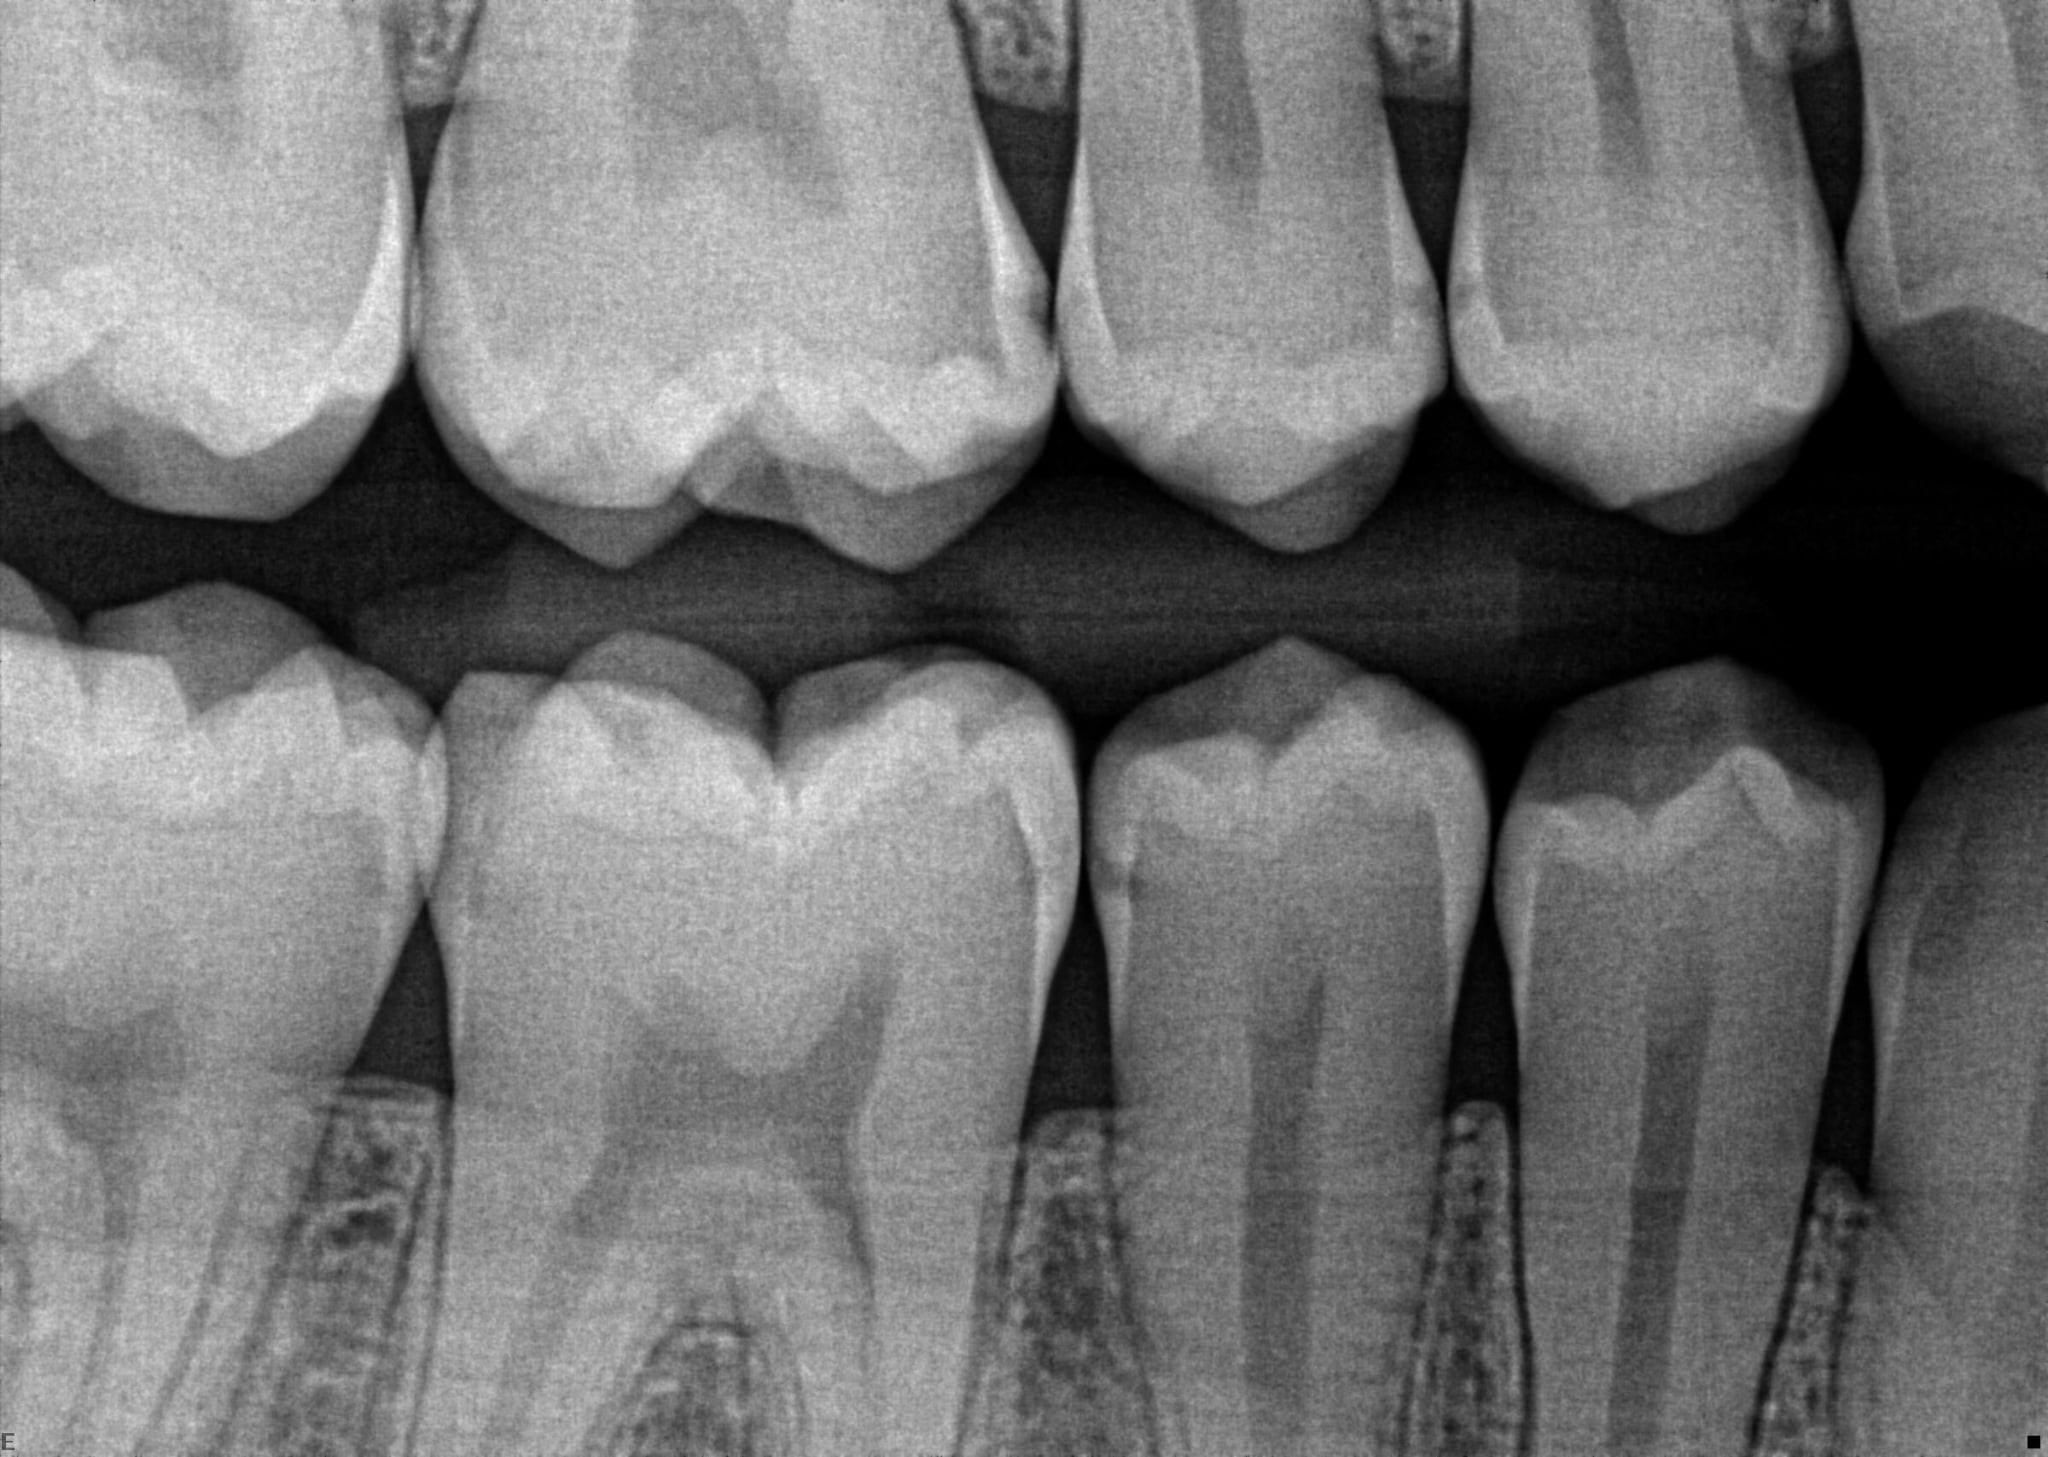

5. In the X ray bellow for which jaw periodontal bone loss is evident?

6. In the X ray bellow for which jaw periodontal bone loss is evident?